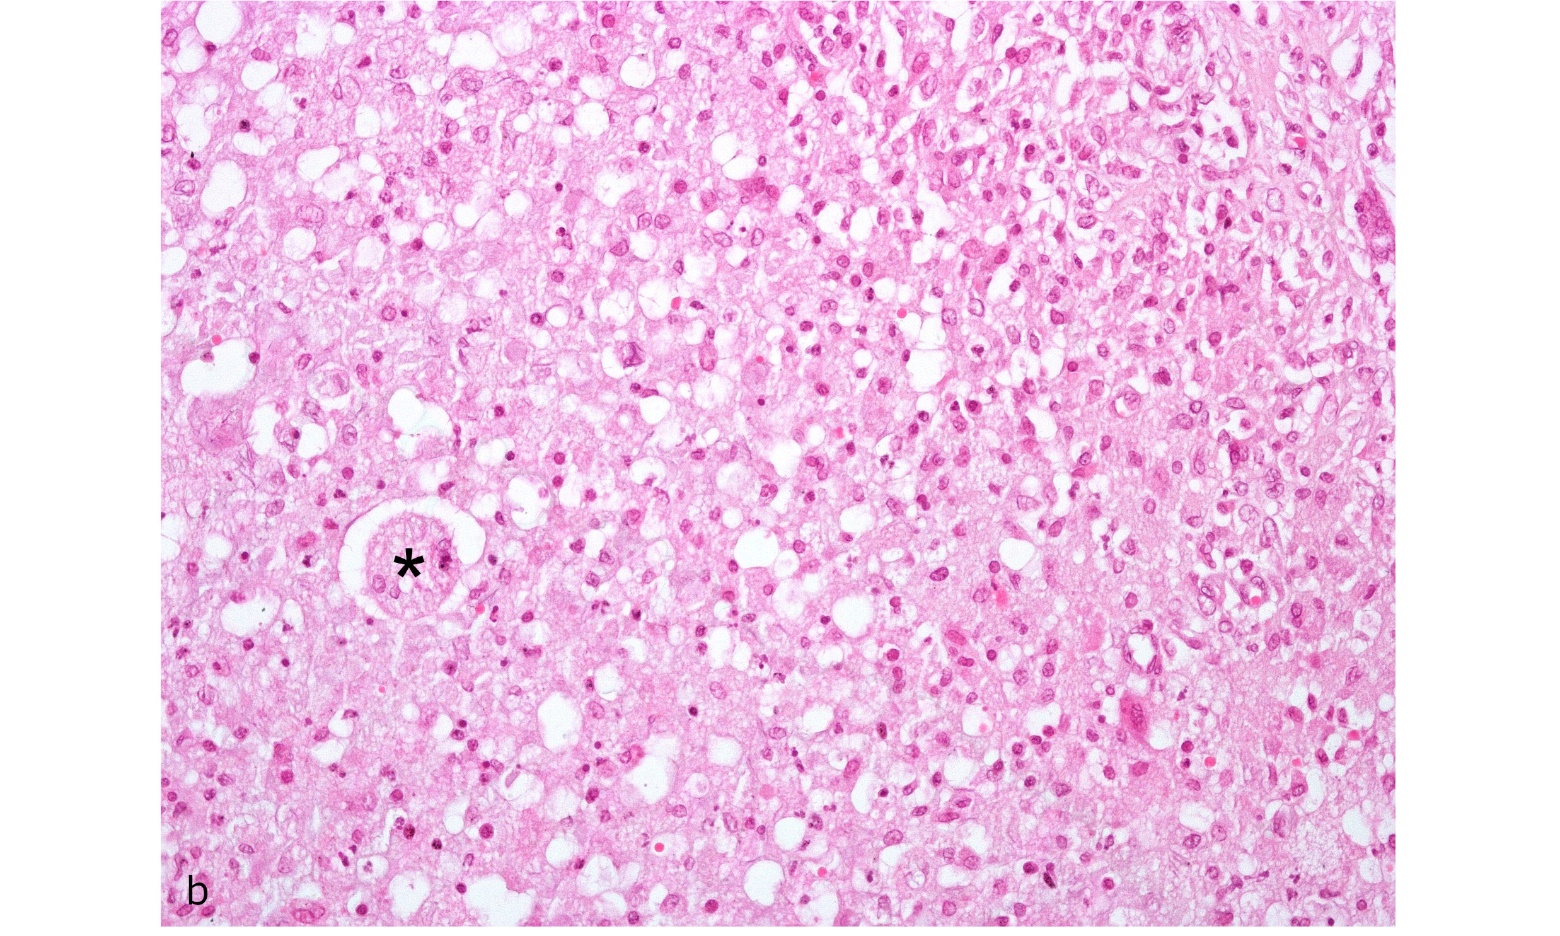

Figure. 2b. Testicle : Detail of boxed area in A showing giant cell (*) and granulomatous inflammatory infiltrate. Hematoxilin/eosin, 200X magnification.

Contrary to the results observed in rabbits (Fort et al. 2012) infected with B. suis biovar 1, the inoculated armadillos did not show macroscopic lesions. In the histopathological studies, lesions were observed only in the epididymis tail of armadillo (B1); this was identical to the lesions observed in domestic species (Foster, 2007). The presence of Brucella in the epididymis and the lesions found in one of the infected animals could be associated with infertility problems in affected armadillos. No histopathological changes were observed in organs from armadillos (A1, B2, B3, and B5) or changes were too minor (e.g., slight infiltration of neutrophils or lymphocytes) to be associated with the infection. However, isolation of B. suis from most organs corroborated the presence of infection in these animals. The discrepancy in the lesions between species could be related to a variation in the pathogenesis of the infection. Future studies are needed to determine the pathology associated with long-term infection of B. suis in armadillos.